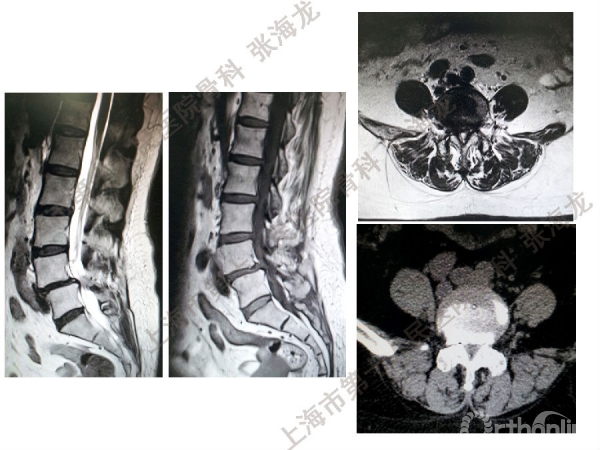

2008年3月至2010年8月,上海市第十人民医院骨科随访49例腰椎滑脱症(峡部裂型和退变型)患者,对比23例微创手术MIS-TLIF和26例开放手术治疗腰椎滑脱症的临床及影像学结果,进行了回顾性研究。

研究发现,Wiltse入路Mis-TLIF更直接的暴露峡部及关节突,对脊柱稳定性的影响较小;彻底松解辅助双重提拉复位Mis-TLIF,对于峡部裂型滑脱有较好的复位效果;对于峡部裂型滑脱,提拉复位在影像学参数上有一定优势;与原位融合相比,ODI.VAS.JOA无明显差异(样本量有限);对于退变性滑脱,单纯撑开椎间隙与原位融合可以获得较好疗效。